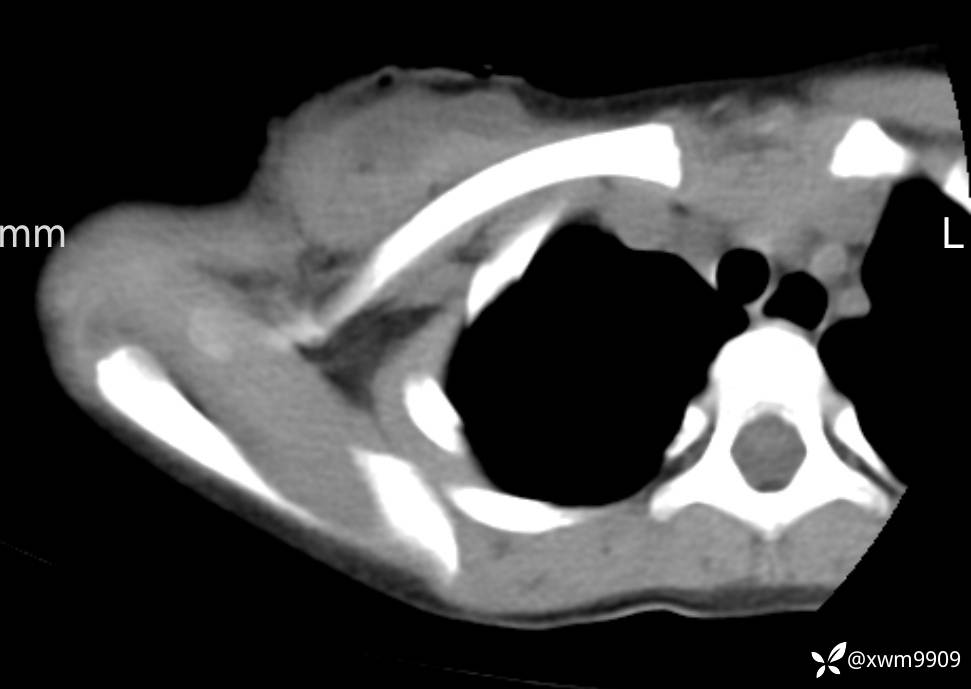

2024-03-20,女,6岁。因“发现右侧胸部肿物伴疼痛1天”入院。

1、患儿为女性儿童,无明确外伤史(此处与门诊病史相反),现发现右侧胸部肿物、疼痛。

2、现病史:家属代诉昨日洗澡时发现右胸肿物,压痛明显,查DR:未见明显异常,自行予云南白药,症状稍好转。临床拟:锁骨周围血肿收入院。

3、查体,右锁下方可及一约5x6Cm肿物,软丶边清丶未见明显发红,肤温不高,压痛明显,不可推动,稍有波动感。其他无特殊。

CT:

2、CT、MR肿块内可见液-液平面,常见有哪些疾病。